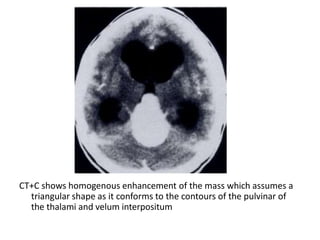

a) Pineocytoma :

-No male predilection

-Older age group, mean age 35 years

-Slow growing, dissemination is uncommon

-No helpful imaging features, cannot be

distinguished by imaging features from a

Pineoblastoma

CT+C shows homogenous enhancement of the mass which assumes a

triangular shape as it conforms to the contours of the pulvinar of

the thalami and velum interpositum

a) Pineocytoma : -Nomale predilection -Older age group, mean age 35 years -Slow growing, dissemination is uncommon -No helpful imaging features, cannot be distinguished by imaging features from a Pineoblastoma

• 52.

CT+C shows homogenousenhancement of the mass which assumes a triangular shape as it conforms to the contours of the pulvinar of the thalami and velum interpositum